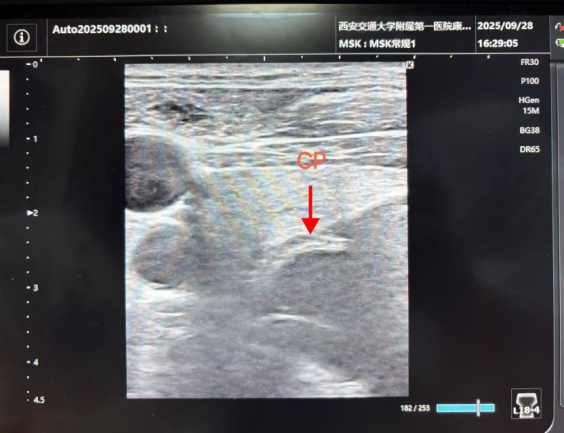

After admission, based on rehabilitation assessment and analysis of videofluoroscopic swallowing study (VFSS) findings, and following discussion with his family, physicians Peng Yu, Guo Jing, Pan Qizhi, and Song Siming performed a botulinum toxin injection for cricopharyngeal achalasia under combined balloon dilation, ultrasound, and EMG guidance.

The technique of botulinum toxin injection for cricopharyngeal muscle dysfunction under combined balloon dilation, ultrasound, and EMG guidance harnesses the mechanical expansion of the balloon dilation to release local fibrotic tissue while enhancing the diffusion effect of botulinum toxin. This triple-guidance approach of combined balloon dilation, ultrasound, and EMG enables precise localization of the cricopharyngeal muscle for accurate injection, ensuring that the botulinum toxin is targeted to the diseased muscle bundles and thereby securing therapeutic efficacy. At the same time, precise localization helps avoid iatrogenic injury to adjacent nerves, blood vessels, and the thyroid, thereby reducing the risks of recurrent laryngeal nerve palsy and perforation. This approach maximizes therapeutic outcomes by ensuring both efficacy and safety.